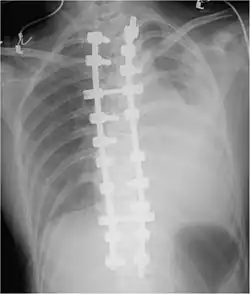

Iatrogenic hemothorax can occur as a complication of heart and lung surgery, for example the rupture of lung arteries caused by the placement of catheters, thoracotomy, thoracostomy, or thoracentesis. The most common iatrogenic causes include subclavian venous catheterizations and chest tube placements, with an occurrence rate of around 1%.[5] Sometimes, a Swan-Ganz catheter causes rupture of the pulmonary artery, causing a massive hemothorax.[6] It can also be caused by other procedures like pleural, lung, or transbronchial biopsies, CPR,[9] Nuss procedure,[10] or endoscopic treatment of esophageal varices.[9] Iatrogenic hemothorax is more common in people who have chronic kidney disease in the intensive care unit.[6]